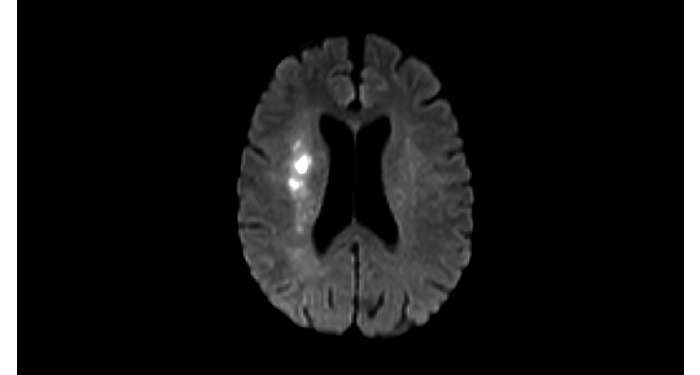

70% of radiologists consider neuro indications to be challenging, mostly due to a lack of appropriate imaging and visualization techniques¹. Philips aims to provide the best possible diagnostic clarity and treatment guidance for all patients with neurological disorders. By leveraging our dStream digital platform, this year, we are introducing, a set of novel imaging and visualization strategies. These may empower you to resolve complex neuro questions with more certainty, as well as unlock new neuro territories in advanced Neurofunctional applications. This is a key step towards elevating neuro diagnostics and ultimately touching more lives with MR imaging. ¹ TMTG Market Survey 2016

New neuro applications

Take a look at our other neuro applications

Clinical cases from nearly every anatomy Explore 100+ clinical cases from your peers around the globe, that showcase how Philips MR digital technology strengthens your imaging needs.